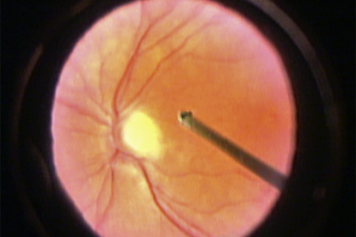

Welcome to Vit-Buckle Academy, a web-based educational portal designed for vitreoretinal surgeons and trainees. Our curriculum is comprised of carefully crafted educational content coupled with high quality, curated videos and figures. Vit-Buckle Academy is the first step-by-step video-based curriculum of how to perform vitreoretinal surgery. The portal also includes resources such as retinal detachment case discussions; a surgical video library; an instrument gallery; a surgical reading list; and more.